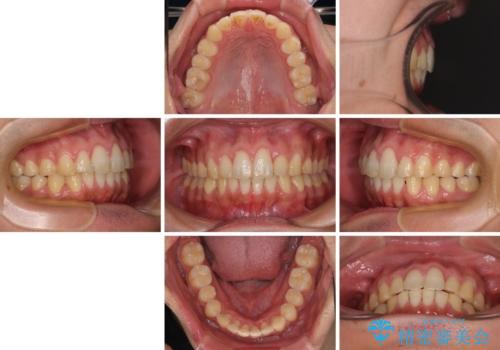

捻れて飛び出した前歯 インビザラインで整った前歯に

- 上下前歯のデコボコと、それに伴う出っ歯を気にして来院された患者様です。

インビザラインによる上下歯列の側方拡大と後方移動、IPR(歯と歯の間を削る)にるスペースの獲得により歯列を整えることとしました。

歯と歯の間を削ることでうまくスペースコントロールでき、また、毎日22時間以上しっかりとマウスピースを装着していただいたので、スムーズに治療が進みました。